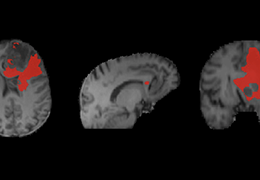

ART-Plan™ Artificial Intelligence Contouring